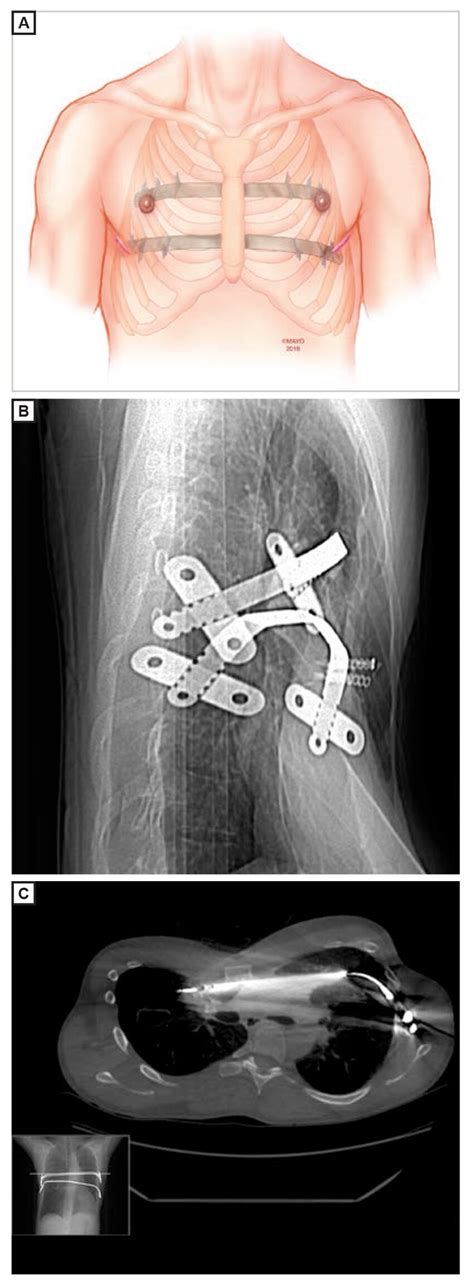

Atliekamos dvi pagrindinės operacijos: mažiausiai invazinis Nuss metodas arba tradicinė Ravitch operacija. Šiuolaikinės skausmo mažinimo technikos, tokios kaip krioabliacija (nervų užšaldymas tarp šonkaulių), leidžia pacientams greičiau atsigauti, sumažina skausmą ir sutrumpina buvimo ligoninėje laiką. Didžioji dalis pacientų išrašomi jau kitą dieną po operacijos.

Pectus excavatum koreguojamas chirurginiu būdu. Pasirenkamas vienas iš dviejų metodų: mažiausiai invazinis Nuss metodas arba tradicinė Ravitch operacija. Operacijos tikslas - ne tik pagerinti kvėpavimo ir širdies veiklą sumažinant mechaninį spaudimą organams, bet ir atkurti natūralią krūtinės formą.

Šiuolaikinės skausmo mažinimo technikos leidžia pasveikti greičiau. Viena naujausių yra krioabliacija - nervų, esančių tarp šonkaulių, užšaldymas, kuris sumažina skausmo pojūčius. Krioabliacija padeda sumažinti stiprų skausmą po Nuss operacijos, todėl trumpėja gulėjimo ligoninėje ir mažiau reikia stiprių vaistų nuo skausmo. Didžioji dalis pacientų išrašomi jau kitą dieną po operacijos. Kai kuriems net neprireikia vaistų nuo skausmo, o kiti jų vartoja tik 1-2 dienas.